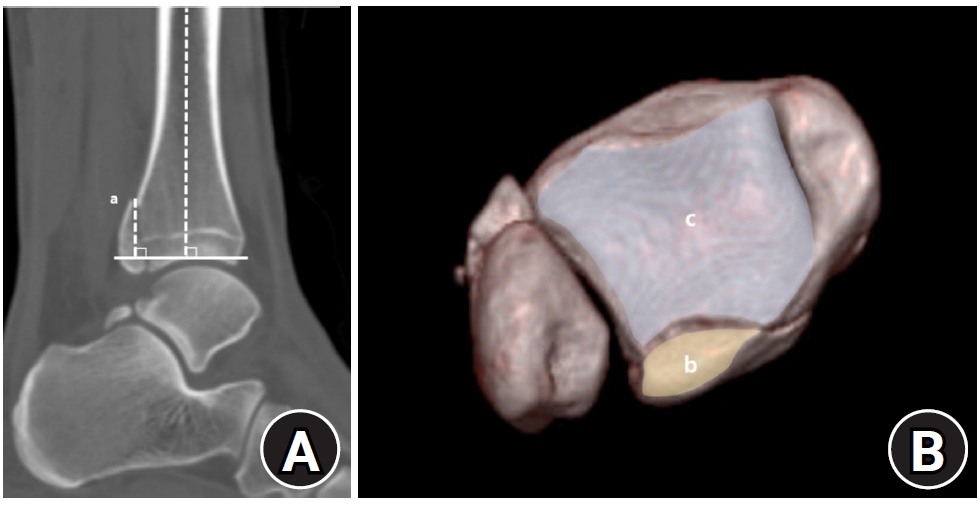

Posterior malleolar fracture morphology was classified according to the Haraguchi and Bartonicek systems (Figs. 2, 3) [19,20]. The peak height of the posterior malleolar fracture was measured as the vertical distance from the highest point of the distal tibial articular surface to the fracture apex in the sagittal plane (Fig. 4A). The articular surface area of the posterior malleolar fragment was calculated using the region of interest tool in a picture archiving and communication system (Maroview 5.4; INFINITT Healthcare) (Fig. 4B). All quantitative radiographic measurements were performed by two orthopedic surgeons; mean values were used. For categorical variables, disagreements were resolved by consensus.

Fig. 4.

(A) Peak height (a) of the posterior malleolar fracture is defined as the vertical distance from the highest point of the distal tibial articular plafond to the apex of the posterior malleolar fragment on the sagittal plane. (B) The articular surface area (mm2) of the posterior malleolar fracture fragment (b) was measured using the region of interest tool in a picture archiving and communication system. Articular involvement (%) was calculated as the ratio of the fractured area (b) to the total tibial plafond articular surface area (b+c).

Fig. 4. (A) Peak height (a) of the posterior malleolar fracture is defined as the vertical distance from the highest point of the distal tibial articular plafond to the apex of the posterior malleolar fragment on the sagittal plane. (B) The articular surface area (mm2) of the posterior malleolar fracture fragment (b) was measured using the region of interest tool in a picture archiving and communication system. Articular involvement (%) was calculated as the ratio of the fractured area (b) to the total tibial plafond articular surface area (b+c).